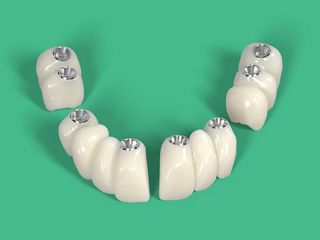

Guided FP1 maxillary rehabilitation with Straumann® STARconcept™ and Straumann iGuide™. A clinical case report by Dr. David Norré, Belgium.

Facially driven Smilecloud design with a focus on preserving tissue and bone. Planned in Smile in a Box and executed with the iGuide protocol; shared pin positions align the drill and prosthetic guides for chairside pickup of the pre-designed provisional. Day-5 follow-up shows the screw-retained provisional in place.

• Temporary bridge pre-fit check using the prosthetic guide and fixation pins.